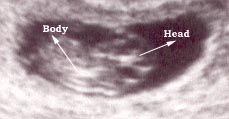

Photo One

This a six week pregnancy and a transvaginal probe was used.

Photo Two

This is a nine weeks pregnancy as seen using a vaginal probe.